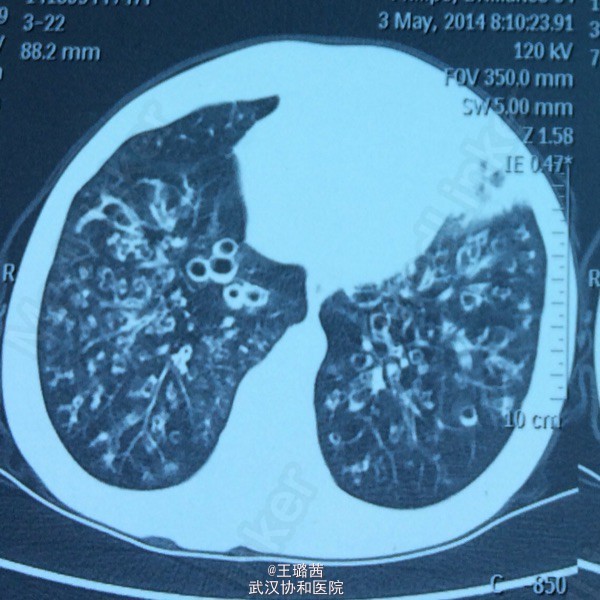

支气管扩张

女,48岁。反复咳嗽咳痰十余年,再发加重十余天。